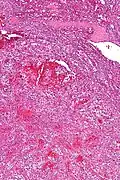

Low magnification micrograph of a littoral cell angioma. H&E stain.

Littoral cell angiomas show in CT scans. They are diagnosed by pathologists by taking a sample of the tumour via Fine Needle Aspiration or Core Needle Aspiration or from a splenectomy. Histologically, they have anastoming small vascular channels and cystic spaces with papillary projections.[2]